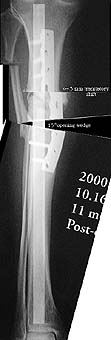

I am a 55-year-old male who suffered a compound fracture of the right tibia and fibula and extensive soft tissue damage, including vascular damage, from the impact of an automobile pinning the leg to a concrete wall in 1971. This occurred while I was a pedestrian. Emergency surgery restored circulation and set the tibia and fibula fragments with no internal fixation (due to concern about infection) and plaster cast immobilization. Later a bone graft was performed, and after physical therapy an apparently full recovery occurred, except a slight varus deformity, reduced vascularity, and reduced range of motion in the ankle. Over the years, the varus deformity worsened to 22 degrees and led to moderate osteoarthritis. To correct the deformity and straighten the tibia, an open-wedge osteotomy was performed in November 1999, with a bone graft from the other iliac crest. Plate fixation was used, as the bone was too hard to ream, so it was impossible to insert a pin. I have used the Exogen ultra-sound device every day since the surgery. Gradual improvement led to enhanced weight-bearing ability, and I have been walking with a cane since April 2000. Although X-rays taken June 16 showed no deformity, the varus deformity has recurred in the October 16 X-rays.

Xrays demonstrate that the medullary canal of the tibia has been obliterated in the vicinty of the fracture. It can be restored with sharp tipped intramedullary guide rods and end cutting reamers. This needs to be carefully done with fluoroscopic guidance.

A Photoshop mockup (without necessary plate removal) is included for your analysis. This of course is much easier to do on a computer than in vivo. Vascular and soft tissue concerns may prevent immediate full correction. That's where a case can be made for a preliminary, gradual and closely monitored deformity correction with external fixation.